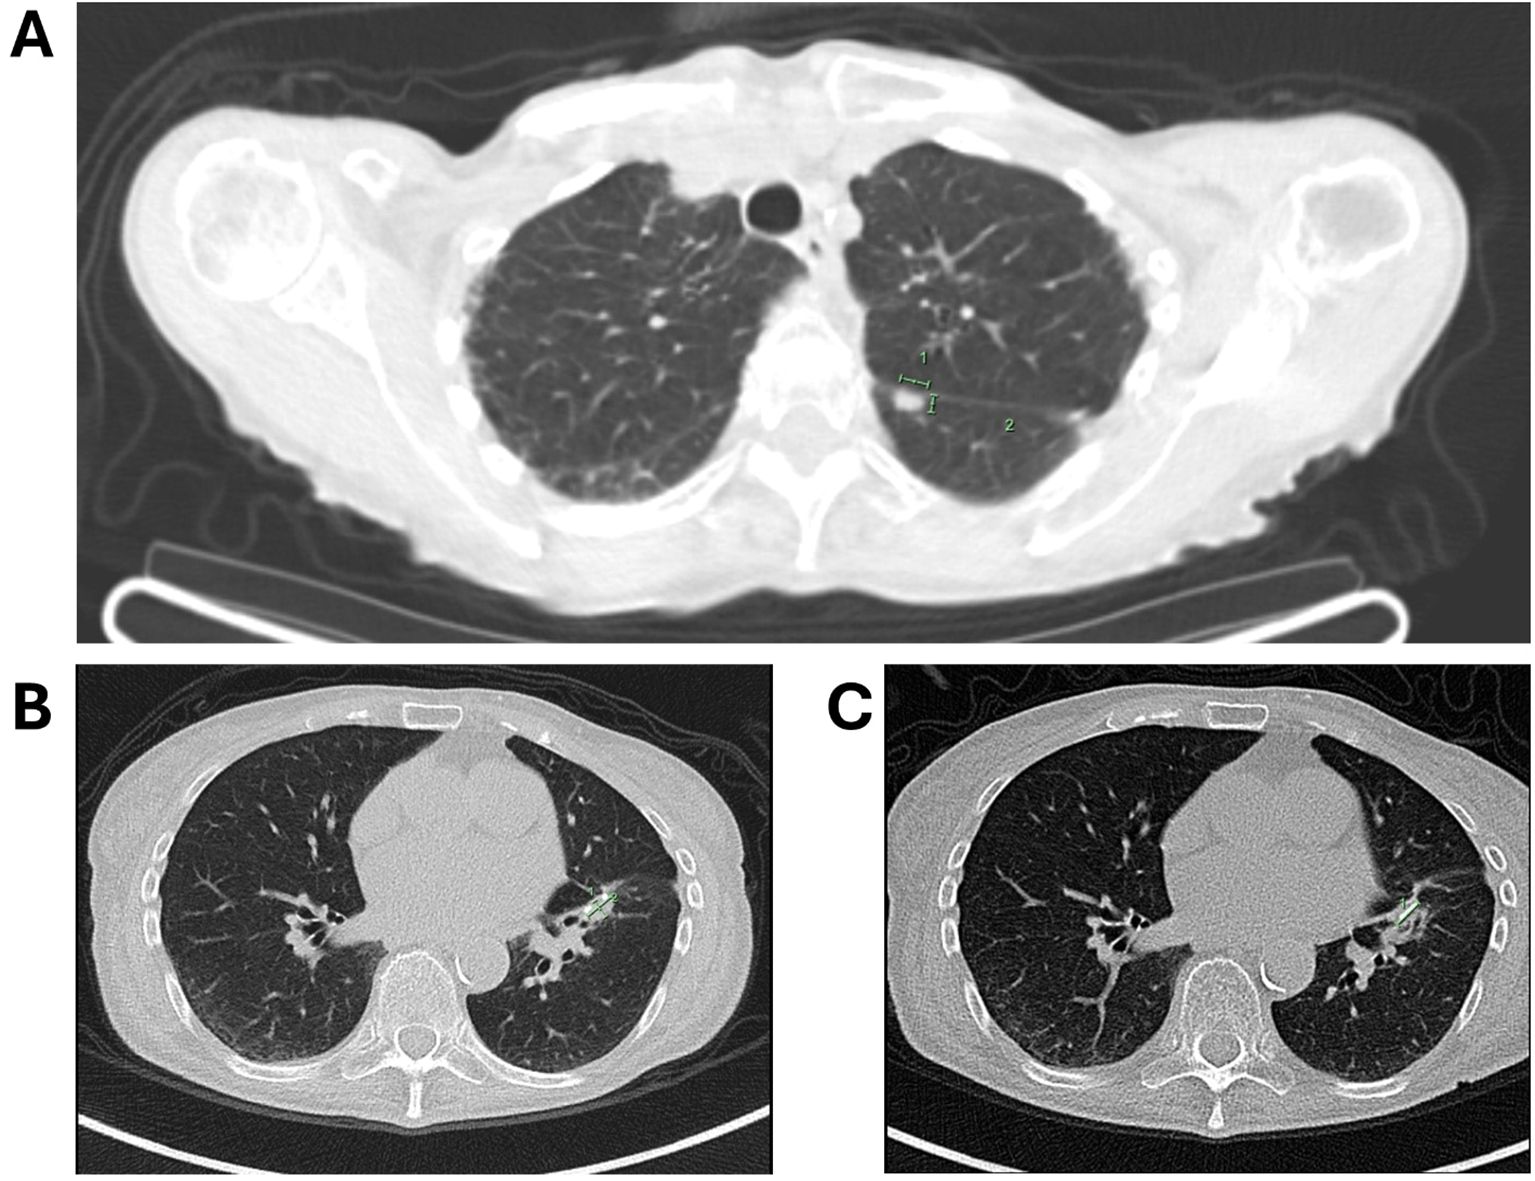

A CT scan revealed an 8.7 × 4.5 × 5.3 cm pancreatic mass. A comparative analysis of prior imaging (Figure 1A) and the most recent scan (Figure 1B) showed significant morphological changes over an 8-year period. Notably, serum CA 19–9 was significantly elevated at 5542 U/m, but liver function tests were normal.

Figure 1. CT imaging comparison demonstrating an 8.7 × 4.5 × 5.3 cm pancreatic mass. (A) earlier scan; (B) a scan after 8 years, illustrating significant morphological changes over 8 years; (C) imaging of a solitary lung lesion indicative of early metastatic spread; (D) CT scan demonstrating a second lung lesion treated with radiotherapy.

The patient was diagnosed with borderline resectable pancreatic cancer and was referred for pseudoneoadjuvant chemotherapy. Treatment with gemcitabine and nab-paclitaxel resulted in a marked reduction in tumor size and CA 19–9 level, which fell to 58 IU/mL (Figure 1C). However, chemotherapy was discontinued after 2.5 cycles due to severe skin toxicity.

During routine follow-up, approximately 12 months after surgery (around 18 months from initial diagnosis), serial imaging and biomarker assessments showed disease progression. A solitary lung lesion was identified and successfully resected which was confirmed to be metastatic pancreatic cancer (Figure 1C). Later, a second pulmonary lesion was detected and treated with radiotherapy (Figure 1D), with subsequent imaging demonstrating a positive therapeutic response (Figure 2A). Despite these interventions, recurrence of the initial lung lesion occurred (Figure 2B), necessitating repeat radiotherapy, which again yielded a favorable response (Figure 2C). Eventually, new PET-avid pulmonary lesions were detected, coinciding with a rise in CA 19–9 levels, suggesting further disease progression.